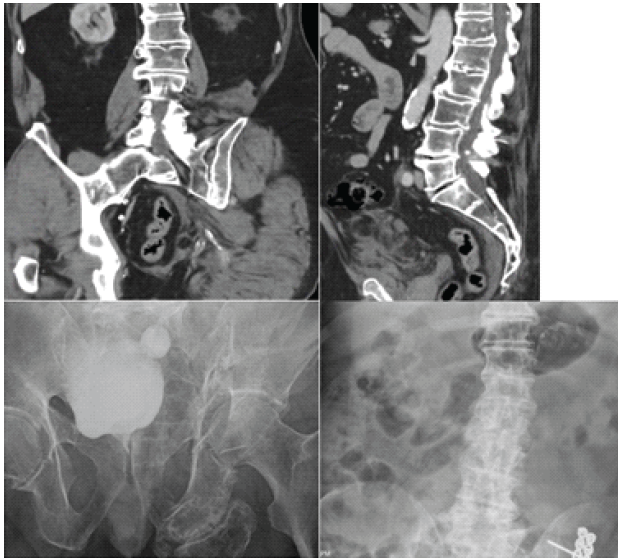

A 78-year-old male with previous medical history of rheumatoid arthritis, Type 2 diabetes mellitus, and AS presented for left THA due to non-union of ORIF of left acetabular fracture secondary to fall off of a ladder and post-traumatic arthritis. The patient had a pelvic X-ray significant for acute comminuted fracture of the left acetabulum with post-traumatic protrusion deformity that resulted in subsequent ORIF of left acetabulum over a year before the THA; pre-operative CT abdomen and pelvis and post-operative X-ray abdomen was not significant for vertebral fracture at this time (Fig. 1).

Figure 1: (Top left) pre-operative coronal computed tomography (CT) abdomen and pelvis significant for left acetabulum fracture and negative for lumbar fracture. (Top right) pre-operative sagittal CT abdomen and pelvis negative for lumbar fracture. (Bottom left) anterior-posterior (AP) X-ray film significant for left acetabulum fracture before open reduction and internal fixation (ORIF). (Bottom right) AP X-ray 1 week s/p ORIF of left acetabulum fracture, significant for lumbar vertebral degenerative changes and negative for lumbar fracture.